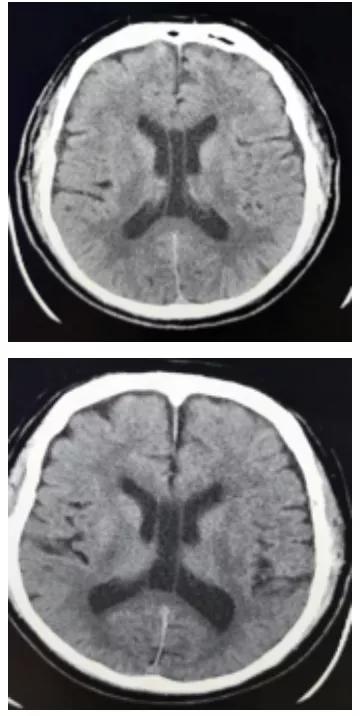

透明隔间腔是在颅内两层透明隔之间形成的腔隙,它的上界为胼胝体体部,前下方为胼胝体膝部及嘴部和前联合,底部和后方为穹窿。透明隔间腔被认为是人脑发育过程中的正常结构,通常在出生后的几个月内闭合,但该结构亦存在于少数成人中。但是,将透明隔间腔称为"第五脑室"是不正确的,因为它的内壁未衬有室管膜细胞,其内含有的液体也通常与脑室系统不同,因此透明隔间腔不具备脑室的组织结构特征。

透明隔腔(CSP)的前上方为胼胝体,后下方为穹隆。侧壁即透明隔小叶。透明隔腔≤3mm,描述可见透明隔腔。

透明隔腔增宽是透明隔腔≥3mm,直径<10mm,描述可见透明隔腔增宽,透明隔的两壁呈前后平行排列,边界清晰,或内凹,对周围组织无压迫,为正常生理变异,临床无症状。透明隔腔≥10mm,描述可见透明隔腔明显增宽。